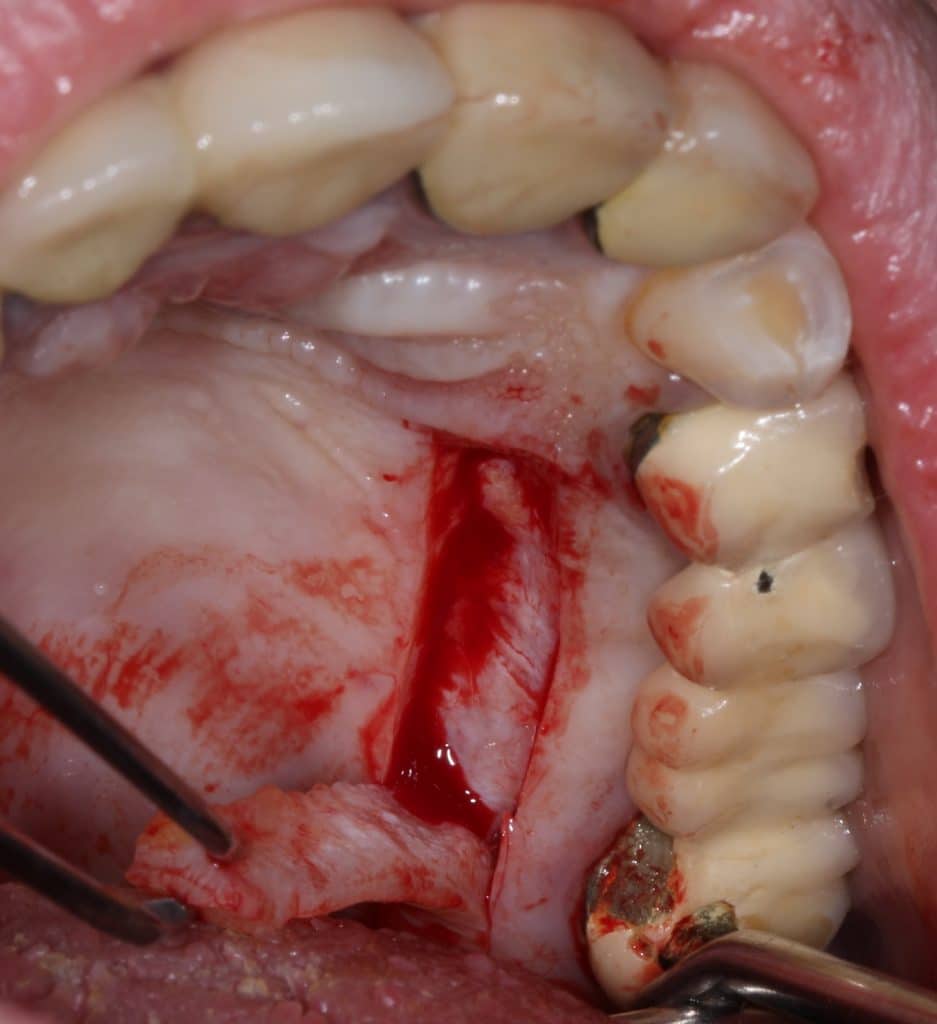

Removal of 2 broken implants with piezoelectric instrument

Gingival and connective tissue graft harvested from the palate